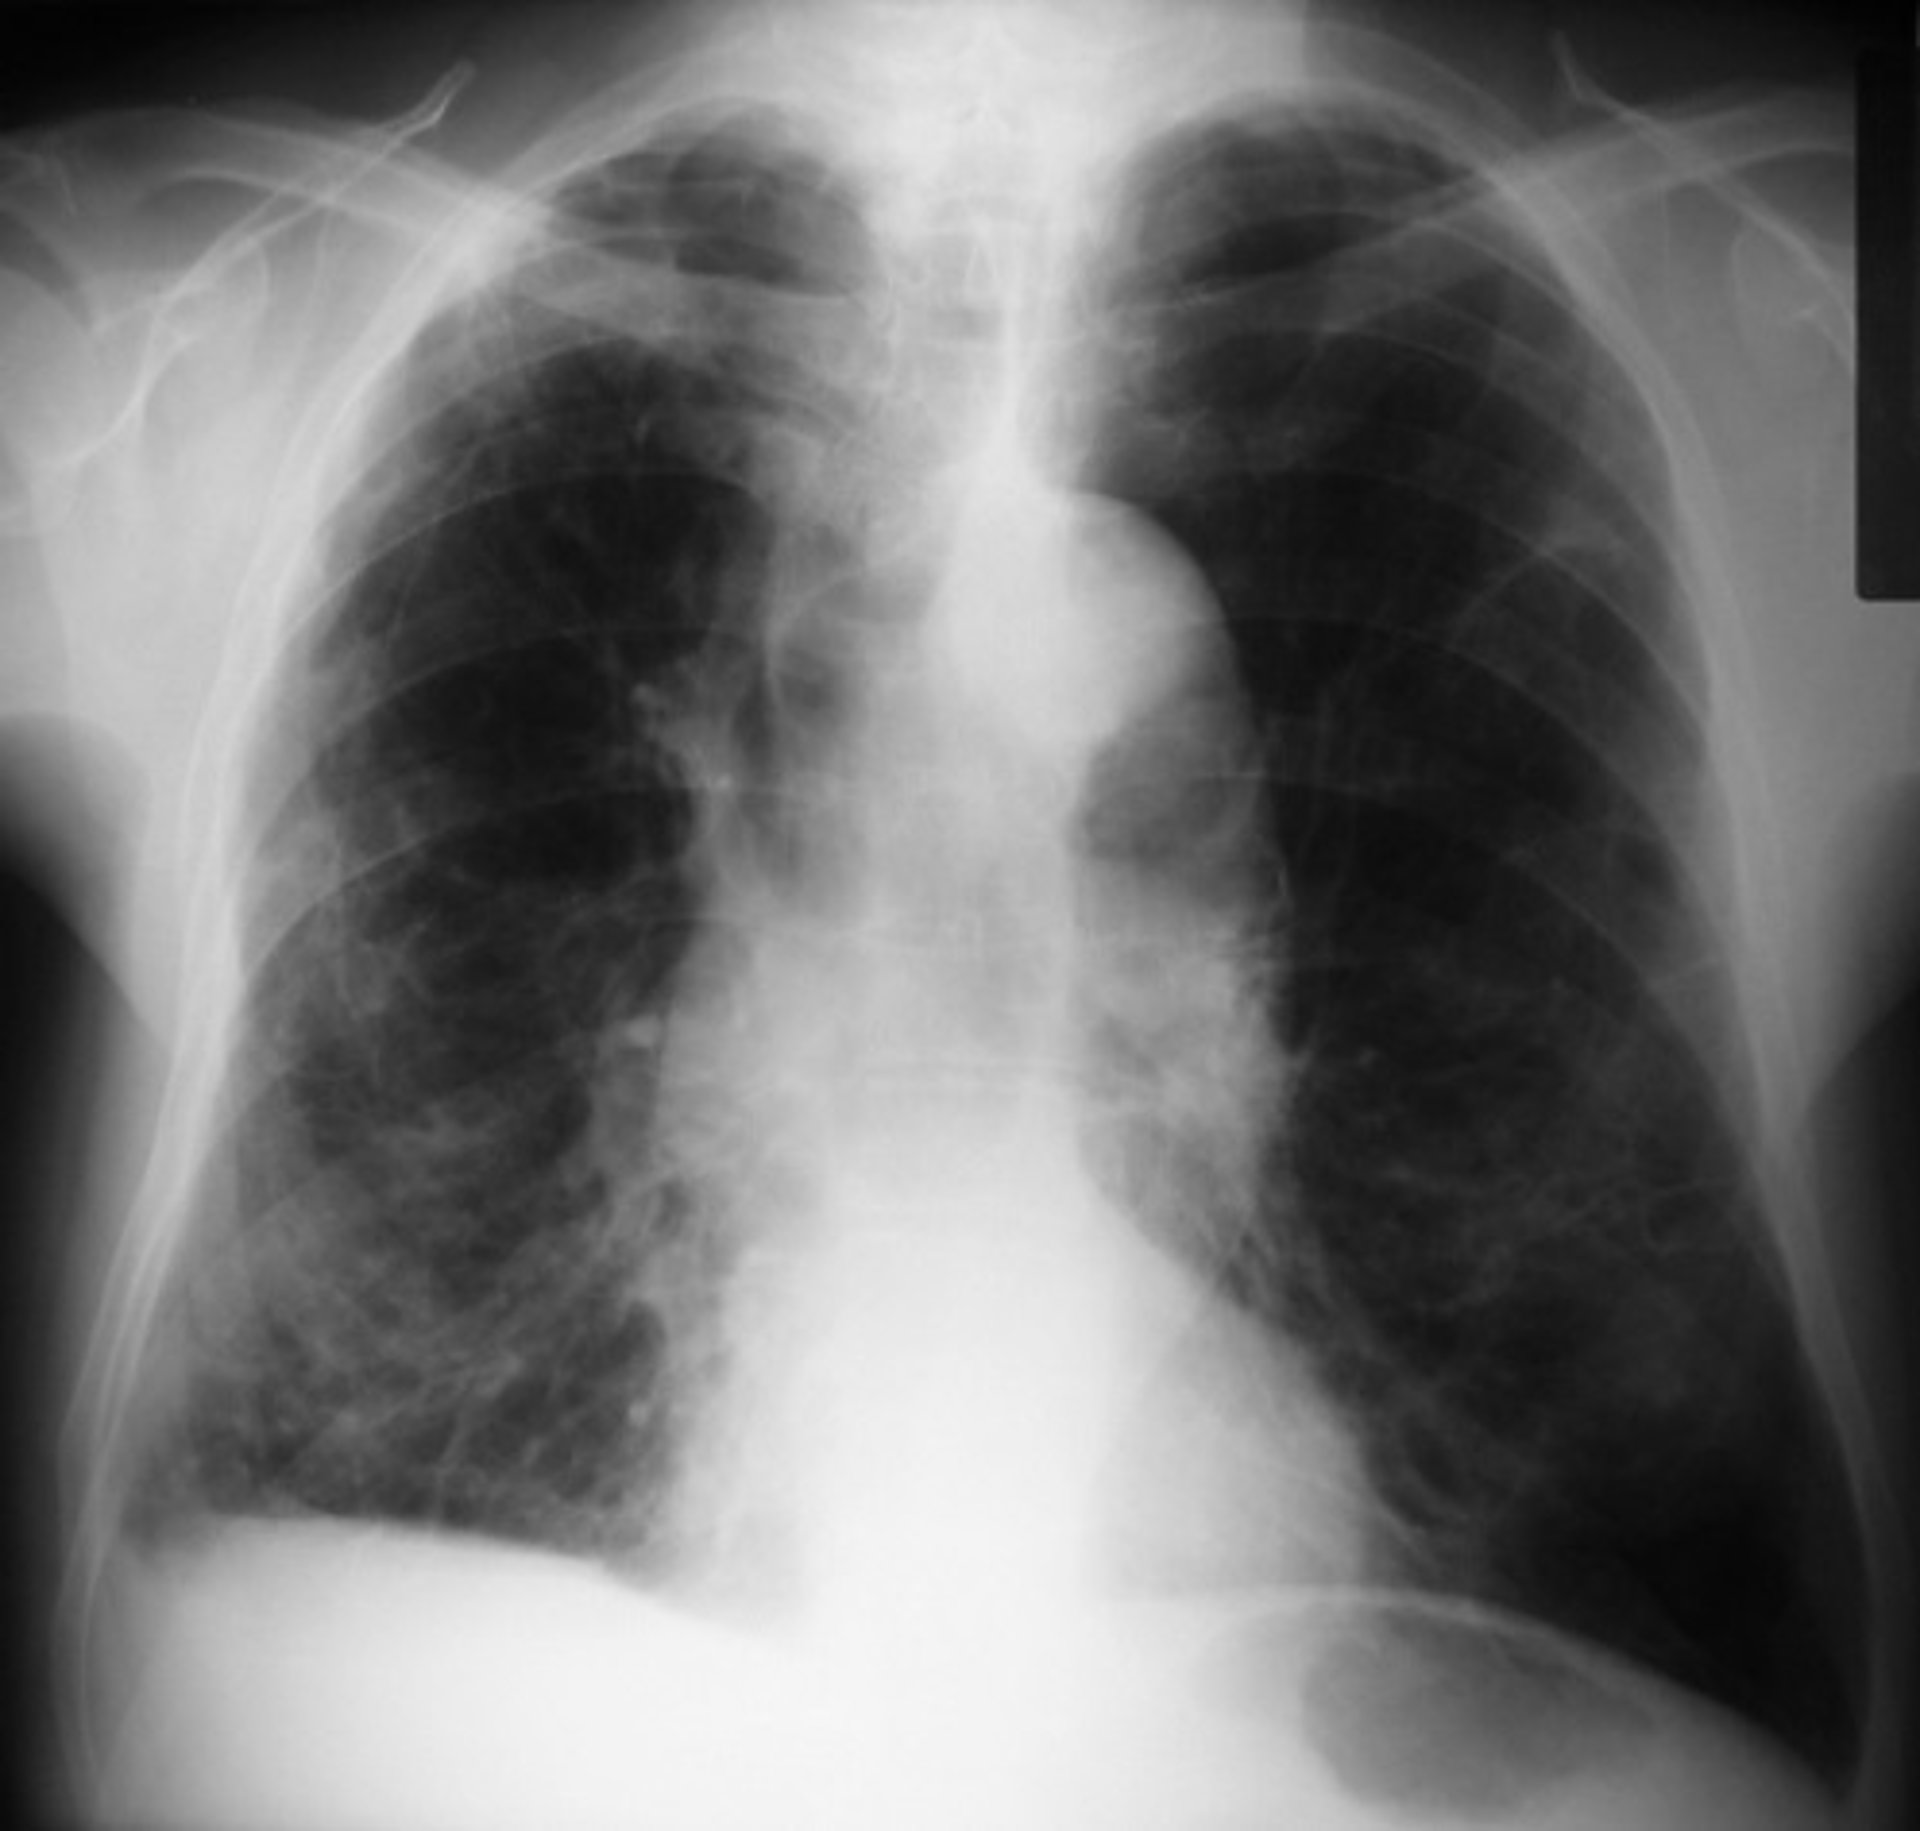

EPOC - FLICKR//PICASA - Archivo

Los investigadores ahora planean repetir las pruebas en las camisas inteligentes con pacientes con enfermedad pulmonar obstructiva crónica (EPOC), pero creen que la tecnología también podría ayudar en otras afecciones respiratorias como el asma, la fibrosis quística o después del trasplante.